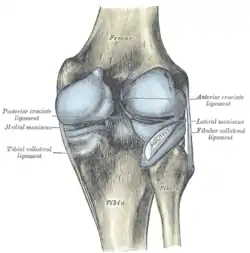

Intracapsular

The knee is stabilized by a pair of cruciate ligaments. These ligaments are both extrasynovial, intracapsular ligaments.[17] The anterior cruciate ligament (ACL) stretches from the lateral condyle of femur to the anterior intercondylar area.[13] The ACL is critically important because it prevents the tibia from being pushed too far anterior relative to the femur.[13] It is often torn during twisting or bending of the knee.[18] The posterior cruciate ligament (PCL) stretches from medial condyle of femur to the posterior intercondylar area. This ligament prevents posterior displacement of the tibia relative to the femur.[13] Injury to this ligament is uncommon but can occur as a direct result of forced trauma to the ligament.

The transverse ligament stretches from the lateral meniscus to the medial meniscus. It passes in front of the menisci. It is divided into several strips in 10% of cases.[10]: 208 The two menisci are attached to each other anteriorly by the ligament.[19] The posterior (of Wrisberg) and anterior meniscofemoral ligaments (of Humphrey) stretch from the posterior horn of the lateral meniscus to the medial femoral condyle. They pass anterior and posterior to the posterior cruciate ligament respectively.[13][10]: 208 The meniscotibial ligaments (or "coronary") stretches from inferior edges of the menisci to the periphery of the tibial plateaus.

Extracapsular

The patellar ligament connects the patella to the tuberosity of the tibia. It is also occasionally called the patellar tendon because there is no definite separation between the quadriceps tendon (which surrounds the patella) and the area connecting the patella to the tibia. [20] This very strong ligament helps give the patella its mechanical leverage [21] and also functions as a cap for the condyles of the femur. Laterally and medially to the patellar ligament the lateral and medial retinacula connect fibers from the vasti lateralis and medialis muscles to the tibia. Some fibers from the iliotibial tract radiate into the lateral retinaculum and the medial retinaculum receives some transverse fibers arising on the medial femoral epicondyle.[10]: 206

The medial collateral ligament (MCL a.k.a. "tibial") stretches from the medial epicondyle of the femur to the medial tibial condyle. It is composed of three groups of fibers, one stretching between the two bones, and two fused with the medial meniscus. The MCL is partly covered by the pes anserinus and the tendon of the semimembranosus passes under it.[10]: 206 It protects the medial side of the knee from being bent open by a stress applied to the lateral side of the knee (a valgus force).[10]: 206

The lateral collateral ligament (LCL a.k.a. "fibular") stretches from the lateral epicondyle of the femur to the head of fibula. It is separate from both the joint capsule and the lateral meniscus.[10]: 206 It protects the lateral side from an inside bending force (a varus force). The anterolateral ligament (ALL) is situated in front of the LCL.